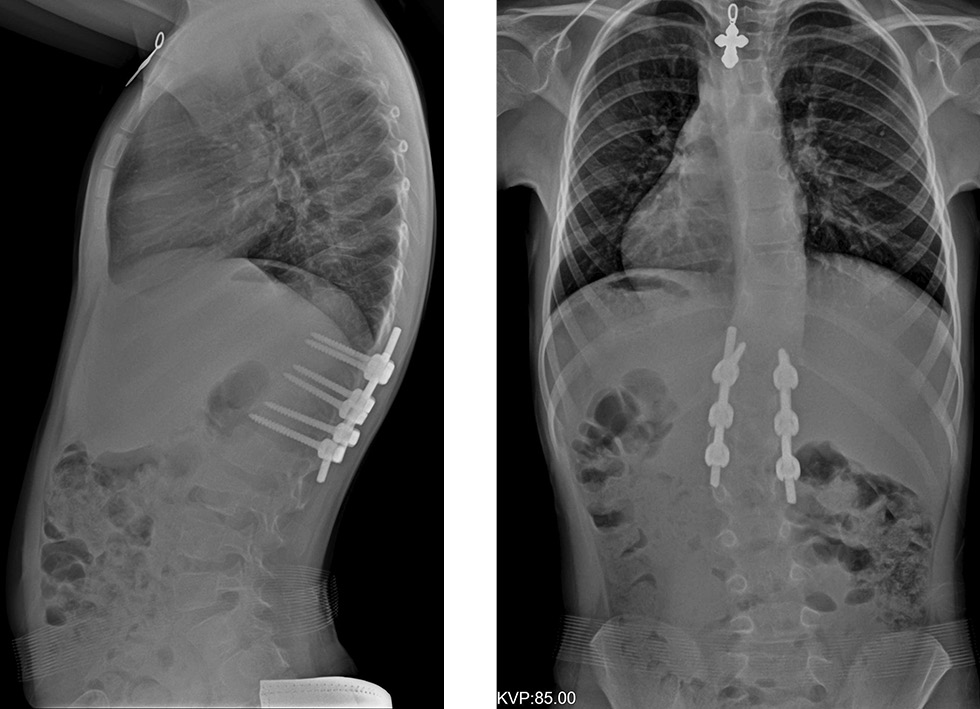

Клиническое наблюдение. Ребенок В., 6 лет, с врожденным кифосколиозом на фоне заднебокового полупозвонка L2, через 5 дней после оперативного лечения снабжен функционально-корригирующим корсетом на туловище. На рентгенограммах позвоночного столба до операции (рис. 4) заднебоковой полупозвонок на уровне L2 с углами деформации, поясничная левосторонняя локальная сколиотическая дуга на уровне полупозвонка — 36°, правосторонняя компенсаторная грудная дуга — 30°. Величина локального кифоза — 23° по Cobb. Величина грудного кифоза — 51° по Cobb.

На рентгенограммах после оперативного лечения отмечалась радикальная коррекция локальной врожденной деформации позвоночника грудного отдела, положение металлоконструкции правильное, стабильное. Правосторонняя компенсаторная сколиотическая противодуга на уровне позвонков Th11–Th7 величиной 18°.

Результаты ортезирования демонстрирует рис. 5. На рентгенограммах через 6 мес. в функционально-корригирующем корсете положение металлоконструкции в грудном отделе стабильное, произошла коррекция правосторонней компенсаторной противодуги на уровне позвонков Th11–Th7 до величины 6°.

На рентгенограммах через 12 мес. без корсета положение металлоконструкции в грудном отделе стабильное. Потери достигнутой коррекции деформации по сравнению с периодом ортезирования в 6 мес. нет: правосторонняя сколиотическая дуга Th11–Th7 величиной 10° по Соbb. У данного пациента в ходе хирургического вмешательства удалось полностью исправить локальную врожденную дугу деформации, зафиксировав минимальное количество позвоночно-двигательных сегментов и уменьшить величину компенсаторной противодуги. Использование после операции функционально-корригирующего ортеза позволило не только добиться стабилизации компенсаторной дуги противоискривления, но и осуществить коррекцию ее величины. Ребенок до настоящего времени пользуется корсетом и будет находиться под активным наблюдением с периодичностью раз в 3 мес. до завершения периода костного роста.

Рис. 4. Рентгенограммы позвоночника в двух проекциях пациентки В., 6 лет. Врожденный кифосколиоз на фоне заднебокового полупозвонка L2, после оперативного лечения

Рис. 5. Рентгенограммы позвоночника пациентки В., 6 лет. Врожденный кифосколиоз на фоне заднебокового полупозвонка L2: а — через 6 мес. в функционально-корригирующем корсете; б — через 12 мес. в положении стоя без корсета